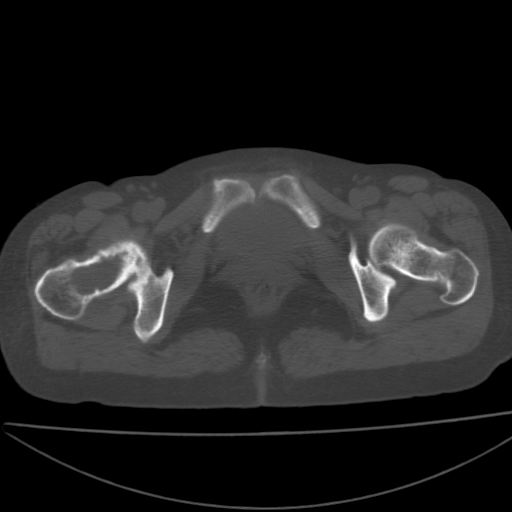

以下是引用xiaoniu在2008-9-6 8:22:00的发言:[br]右侧股骨颈囊性低密度,囊壁边缘硬化,中年妇女,首先考虑:骨囊肿。其次考虑动脉瘤样骨囊肿。[br][br][br][本贴已被 xiaoniu 于 2008-9-6 9:04:54 修改过]